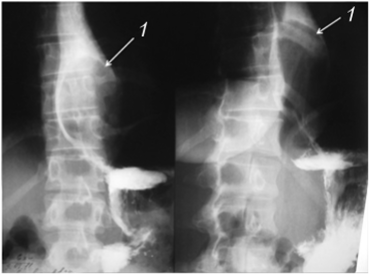

При рентгенологическом исследовании внутрипросветные опухоли представляются в виде локального утолщения одной из складок (на ранней стадии развития) или округлого дефекта наполнения на широком основании или на ножке. Очертания его резкие, иногда мелковолнистые. Перистальтика не нарушена, задержка контрастной массы бывает лишь при больших размерах новообразования или при локализации его в брюшной части пищевода над кардиальной частью желудка (рис. 10.1).

Рис. 10.1. Рентгенограмма пищевода с лейомиомой в его средней трети

При глотании образование смещается вместе со стенкой пищевода в проксимальном направлении.

При внутристеночных опухолях складки слизистой оболочки сохранены, они могут лишь огибать опухоль, также они обычно сужены или уплощены. Сама опухоль может выявляться по краевому дефекту наполнения с ровными контурами. При крупных опухолях наблюдается веретенообразное расширение вышележащих отделов пищевода.